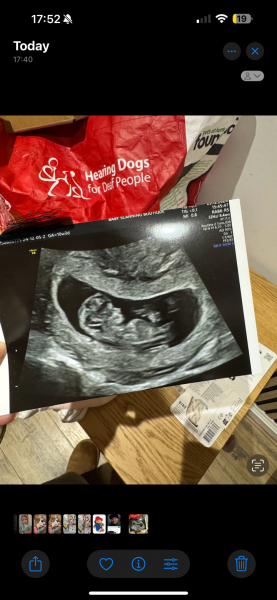

Brownbottle · 09/01/2025 19:43

Glad your scans went so well @JDecember21 and @sellingupslow , lovely scan images!

Mine was good too! Baby measuring a few days ahead so 13 weeks, due date now 17th July!

11DPO positive - but concerned

Brownbottle · 09/01/2025 19:45

Also came back low risk on the three chromosomal abnormalities, looked low on scan and then bloods also low risk (they took about 6 hours?!)